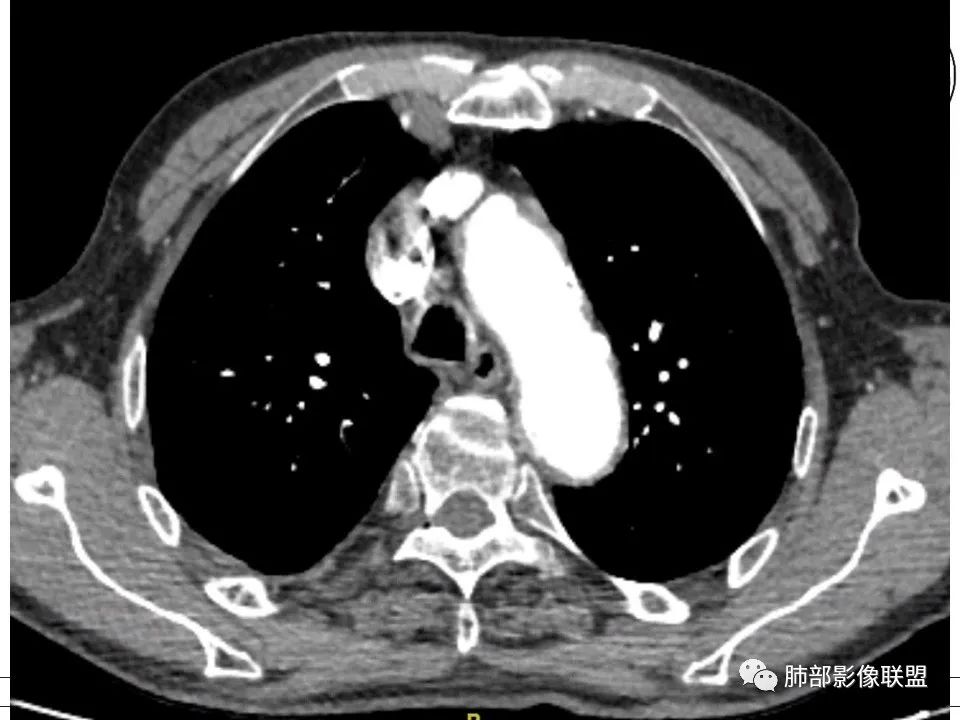

老年男性,右侧胸膜软组织肿块延伸至后纵隔主动脉旁,平扫密度均匀稍高,增强扫描均匀强化,高于肌肉,其内血管走形包绕,部分包绕肋骨,考虑淋巴瘤。病人石棉接触史,不能除外间皮瘤(胸水应该更多)。

右后胸膜下团块,局部膨隆突起,增强扫描有强化,右侧肋间动脉供血,腹膜后主动脉旁亦见团块状软组织密度影,和主动脉分界不清,增强扫描有强化,有石棉工作史,体重明显下降,纵膈淋巴结明显增大,考虑恶性,胸膜间皮瘤?有点疑惑就是胸水不明显,鉴别淋巴瘤。两肺斑片状状影,考虑感染,其中右肺下叶局部结节状影,边缘稍毛糙,周围少许点片状影,首先考虑感染,不除外结核结节和腺癌可能。

肋间动脉漂浮征,淋巴瘤 医学百科网 | YxBaike.Com

黄勇老师讲过,肋间动脉三明治征,淋巴瘤特异性很高。

血管飘浮,三明治,加上纵隔淋巴结多发肿大,部分有融合。基本上定了淋巴瘤了。 医学百科网 | YxBaike.Com

1、老年男性,右侧后胸壁软组织肿块延伸范围较广(至后纵隔主动脉旁),平扫密度均匀稍高,增强扫描均匀强化,其间走行肋间动脉包埋、漂浮(夹心三明治),部分包绕肋骨,肋骨骨质未见明显吸收破坏! 医学百科网 | YxBaike.Com

2、胸膜掀起或尾征,胸壁肋间肌及脂肪间隙浸润,肋间动脉供血。 医学百科网 | YxBaike.Com